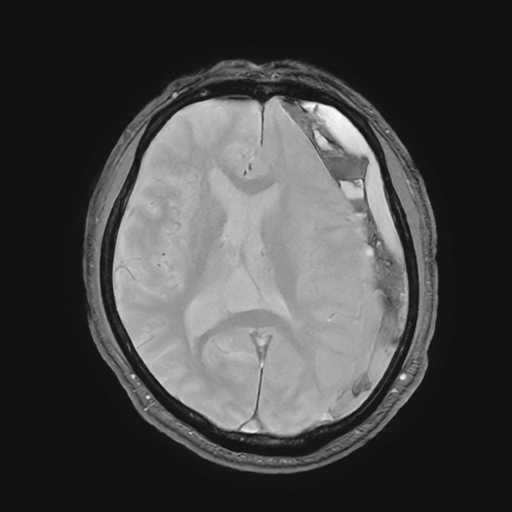

MRI検査

内科領域

頭部

脳梗塞

脳動脈瘤

硬膜下血腫